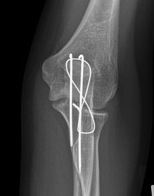

Mayo Classification

A: Non comminuted

B: Comminuted

| Type I | Type II | Type III |

|---|---|---|

| Minimally displaced | Displaced | Trans-olecranon fracture dislocation |

| 10% | 85% | 5% |